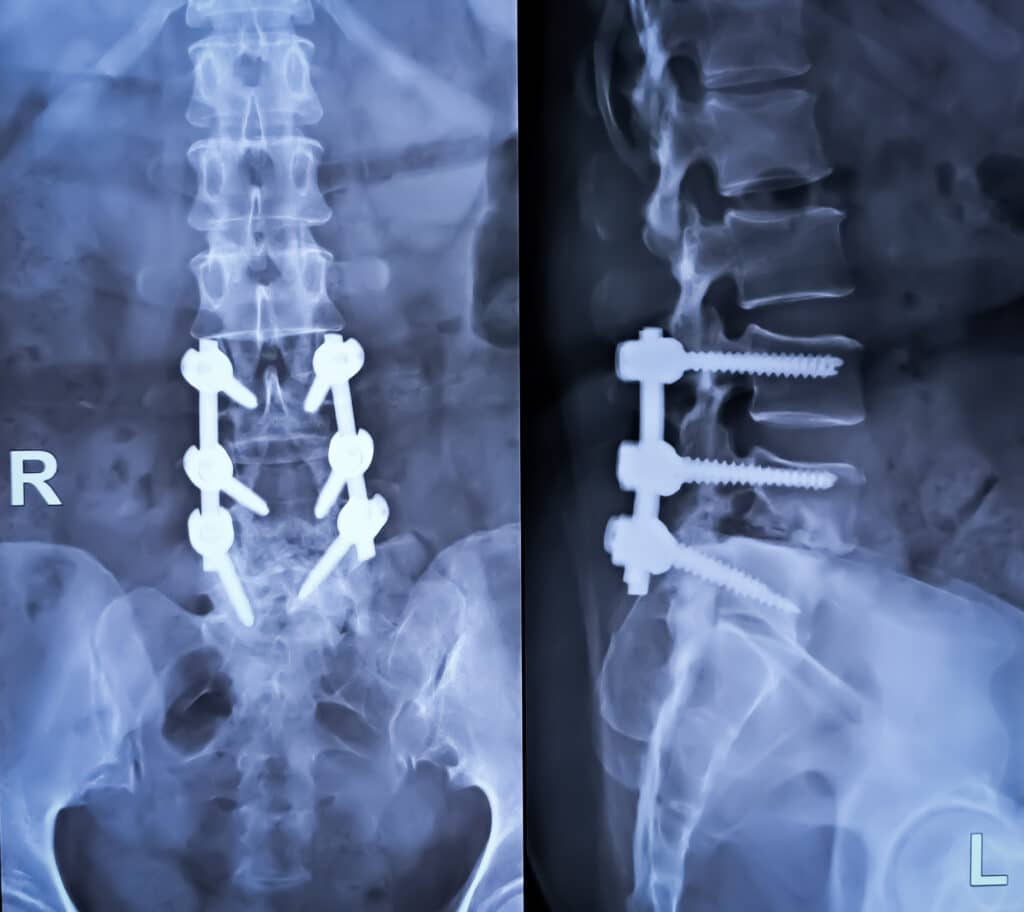

Lumbar Laminectomy vs. Foraminotomy: Imaging Guides the Choice

A pinched lumbar nerveย causes debilitating pain and neurological dysfunction. Fortunately, a surgical solution is possible if the source of the pain can be found. NU-Spine: The Minimally Invasive Spine Surgery Institute is a state-of-the-art pain center near you in New Jersey, Florida, and Pennsylvania. We offer a wide range of surgical proceduresย for patients with spine […]